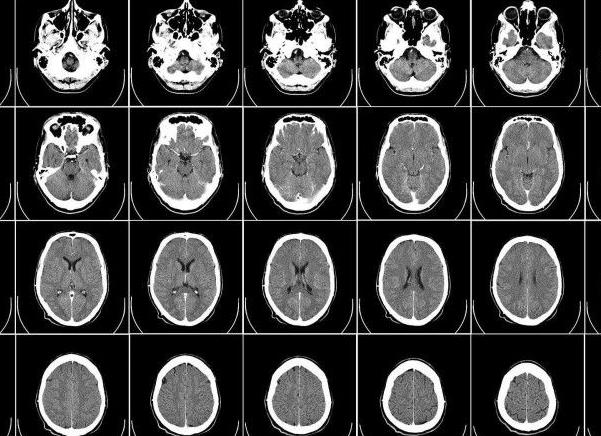

Что показывает МРТ головного мозга?

Мозг человека – сложнейший орган, с ограниченными возможностями для изучения и диагностики патологий. Одним из наиболее эффективных и демонстративных методов исследования мозга является магнитно-резонансная томография. Этот вид диагностических мероприятий назначается наиболее часто для первичного определения нарушений функциональности органа.

При проведении МРТ головного мозга используются различные методики, выбор каждой из них обусловлен исследуемой областью или показаниями. Общее обзорное исследование позволяет получить разветвленное изображение всего органа, его отдельных частей, отследить кровоток и перемещение внутримозговой жидкости.

Что покажет МРТ

МРТ головного мозга. Что показывает исследование:

• Структурные изменения, нарушения мозговых тканей, сосудов.

• Выявляет признаки инсульта.

• Определяет наличие гематом, тромбов, кровоизлияний, контузионных деформаций с точным местом их расположения.

• Констатирует угрозы рассеянного склероза, продемонстрирует расположение и величину атеросклеротических бляшек.

• Мальформацию, разрывы, аневризмы сосудов.

• Выявит возможные воспалителения в тканях или сосудах мозга.

• В режиме ангиографии специалист определит показатели кровотока, сосудистые изменения и пр.

Обзорное МРТ головного мозга дает врачу возможность определить, насколько структура органа пациента отличается от нормы. Визуализация подтверждает или опровергает подозрения в нарушениях функциональности, активности мозга, демонстрирует изменения после черепно-мозговых травм. Сегодня уже не актуален вопрос, где сделать МРТ головного мозга, связи с наличием аппаратов почти во всех клиниках и стационарах. Более актуальным становится выбор опытного специалиста для прочтения результатов.